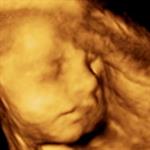

Vitamin dan Mineral Wajib Selama Hamil

Kenali jenis dan manfaat vitamin, serta mineral yang penting untuk kehamilan Anda.... read more